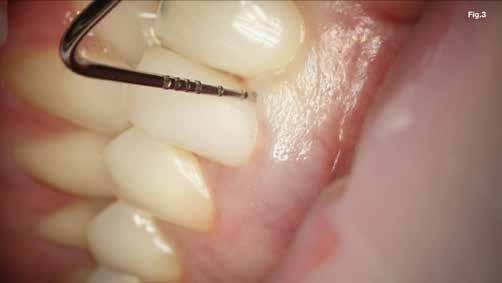

Szépen beállított ideiglenes korona volt jelen, kóros szondázási mélység és szondázási vérzés nélkül. Nem volt jelen sinus tractus (3–5. ábra). Tüneti apikális parodontitis 1. osztály (Von Arx&Cochrane 2001); B osztály (Kim&Kratchman 2005) és korábban elvégzett gyökérkezelés volt a végső diagnózis.

A szubmarginális teljes vastagságú lebenyt két felszabadító bemetszéssel végeztük egy 69-es számú, dupla lekerekített mikropengével (Swann–Morton) (6–7. ábra) A vestibularis csont ép volt, ezért csontablak-technikát alkalmaztunk és végeztünk (6–8. ábra) piezo készülékkel (Woodpecker DTE AI Surgery) és „US1, UC1” (Guilin Woodpecker Medical Instrument Co., LTD) hegyekkel. A blokkot az intraoperatív szakaszok alatt sóoldatban tartot-